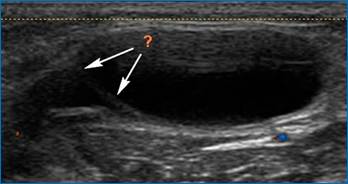

В то время как крупная киста, киста с разрывом капсулы (рис. 4,5) может клинически имитировать острый тромбоз вен нижней конечности.

Рис. 4. Киста Бейкера (ультразвуковая картина разрыва капсулы)